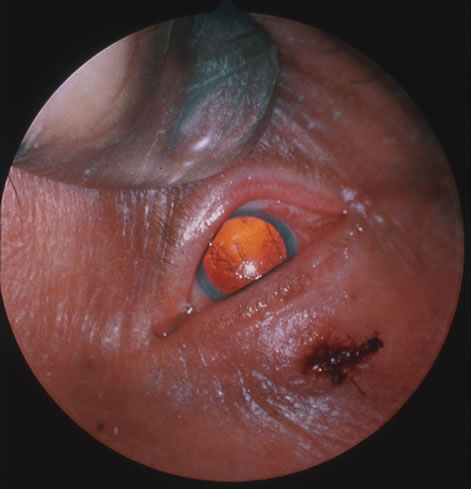

Kaposi's sarcoma is much more frequent in male homosexuals and bisexuals than in other patients with AIDS. Cutaneous lesions are usually red or violaceous, palpable, and nonblanching papules, nodules, or plaques, often appearing on the hard palate, nose, eyelid, and conjunctiva (Fig. 11). Visceral and lymph node involvement is common and often clinically silent. Biopsy specimens show proliferation of small, incompletely formed blood vessels lined by unusually large endothelial type cells, with extravasated red blood cells and infiltrates of spindle-shaped cells. Chemotherapy with etoposide, Vinca alkaloids, or interferon-α may be indicated in advanced cases.28

Fig. 11. The typical lesion of Kaposi's sarcoma on the conjunctiva.